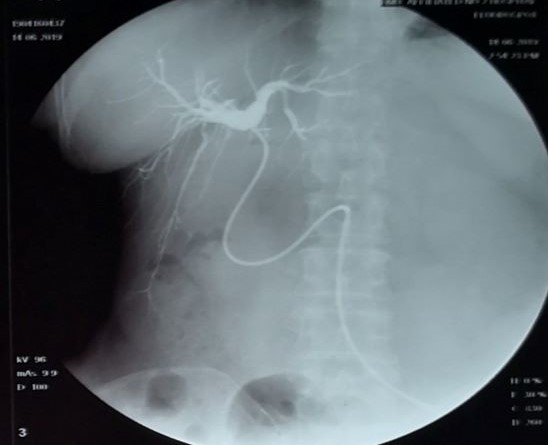

12月5日行“腹腔镜胆囊切除、腹腔引流术”。手术中见大网膜与胆囊粘连紧密,周围有渗出。胆囊床有一迷走胆管伴胆汁溢出,予以钳夹。12月5日手术当天15:10和22:00两次因为疼痛给与曲马多100mg止痛而没有检查原因。手术后第一天(12月6日)8:00病程记录,术后至12月6日7:30腹腔引流黄绿色胆汁液体295毫升,已经考虑到可能肝总管损伤,但是没有及时检查(包括B超、肝功能等)而是准备第二天检查血常规和肝功能。鉴于医院对患者诊疗没有采取有效措施,患者转哈尔滨医科大学附属医院继续诊疗,入院诊断:腹痛待查、胆囊切除术后状态。术前核磁检查肝内外胆管未见明显扩张,诊断胆囊切除术后改变。当天晚上21:30进行腹腔镜下肝总管胆道外引流术、腹腔冲洗引流术。术中见肝门部胆管横断,残端可见钛夹2枚,胆汁自该处溢出。远端胆总管残端被夹闭。进行肝总管胆道外引流。12月13日出院,出院诊断:胆囊切除术后胆汁漏、肝门部胆管损伤。建议3-6月后择期胆肠吻合手术。6月后再次哈尔滨医大附属医院住院,入院诊断:胆囊结石术后、操作中胆管损伤。术前CT显示肝脏弥漫性改变。行肝总管空肠吻合手术,腹腔冲洗引流术后出院。出院医嘱:注意饮食休息,定期拔管。10月8日检查核磁后拔除引流管。